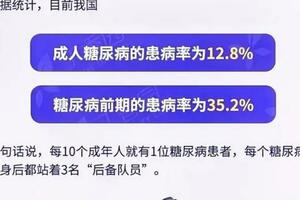

服用丹參粉也是好處多多,第一是雙向調節血糖、血脂,可以治療高血脂、高血壓以及糖尿病等病症。第二是能夠保護心腦血管,抑制動脈硬化,這個功效能夠用來輔助治療冠心病、腦血栓等病症。第三是具有雙向調節中樞神經的作用,對失眠多夢、神經衰弱具有較好地輔助治療效果。第四個功效是是活血散瘀,消腫定痛,可以治療風濕、類風濕、腰腿疼痛等等疾病,另外,長期服用丹參粉還可以保肝抗炎、活血補血。